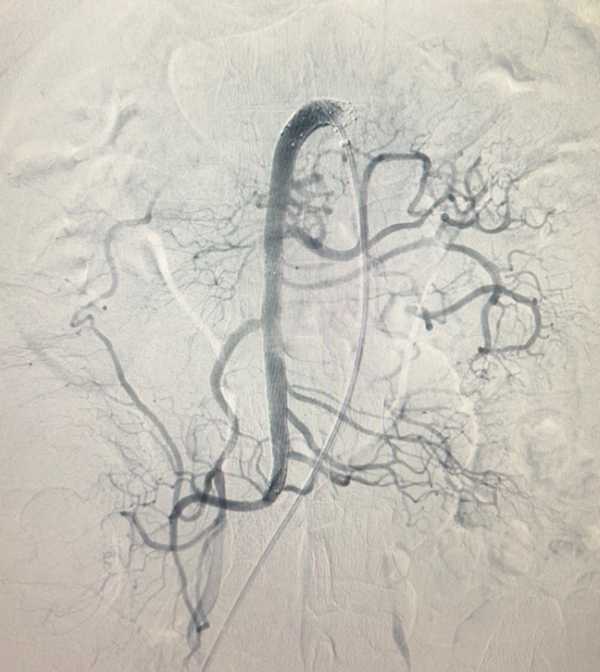

![]() |

| Hình ảnh chụp và can thiệp đặt stent động mạch mạc treo tràng trên: Trước can thiệp bóc tách gần gốc xuất phát, tạo huyết khối gây hẹp lòng và tắc vài nhánh nuôi ruột (hình trái); sau can thiệp đặt stent động mạch mạc treo tái thông hoàn toàn mạch mạc treo, cải thiện tưới máu ruột (hình phải) - Ảnh BVCC |